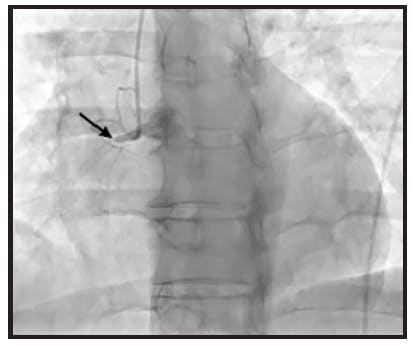

The initial angiogram confirmed an occlusion with extensive thrombus burden of a dominant left circumflex artery and TIMI 0 flow (Figure 1). Power aspiration with CAT RX and Penumbra ENGINE was started after wiring the dominant left circumflex artery. After one pass with CAT RX, the initial occlusion was removed. A second angiogram showed extensive clot burden spread across multiple branches (Figure 2). Each vessel was wired sequentially, delivering power aspiration via CAT RX to the site of each thrombus. A final angiogram revealed complete reperfusion to the dominant left circumflex artery and branches, with TIMI 3 flow (Figure 3).

A 65-year-old man presented emergently with an inferior wall MI. The initial angiogram confirmed a distal occlusion of the RCA with TIMI 0 flow and extensive clot burden (Figure 1).